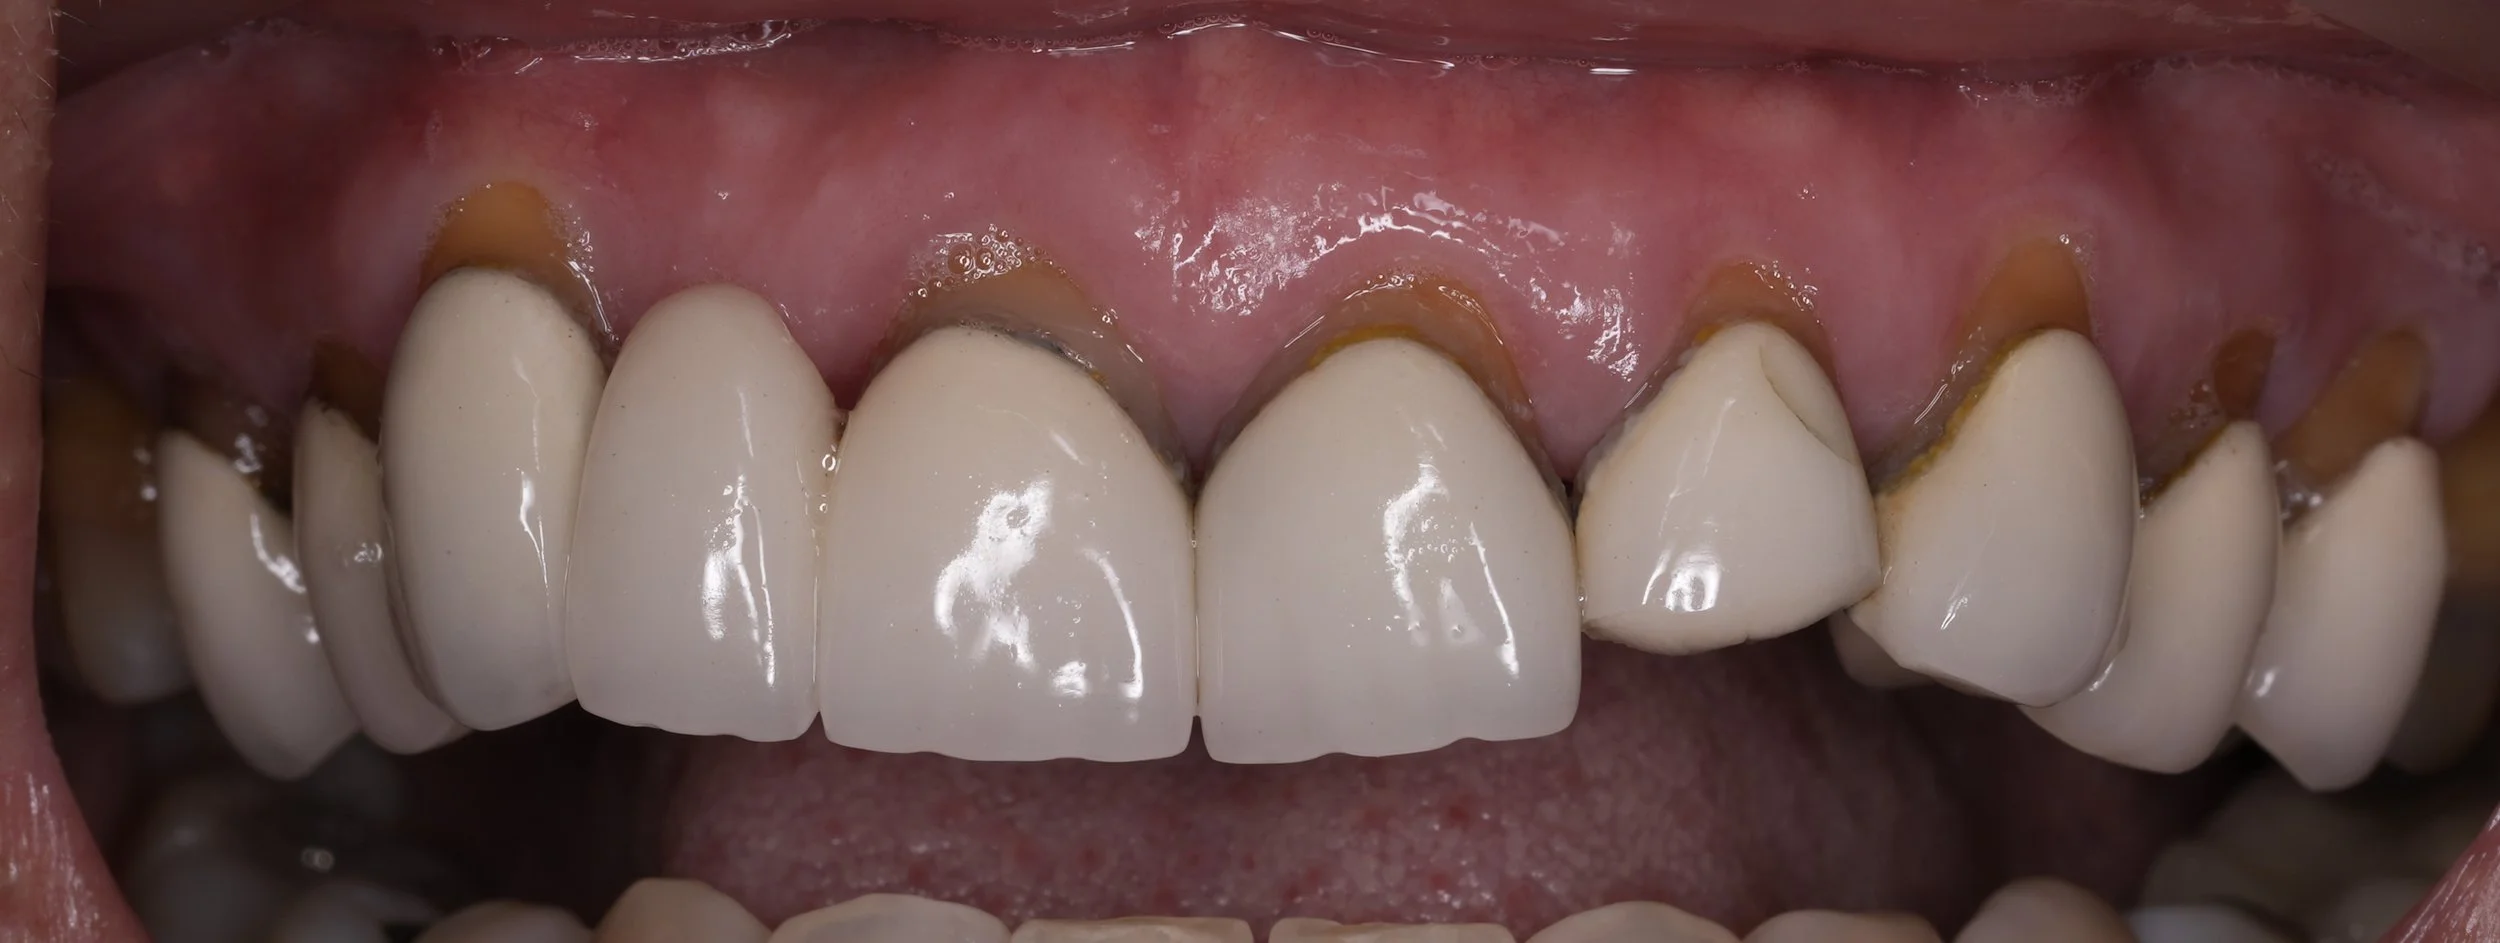

Fixed pros